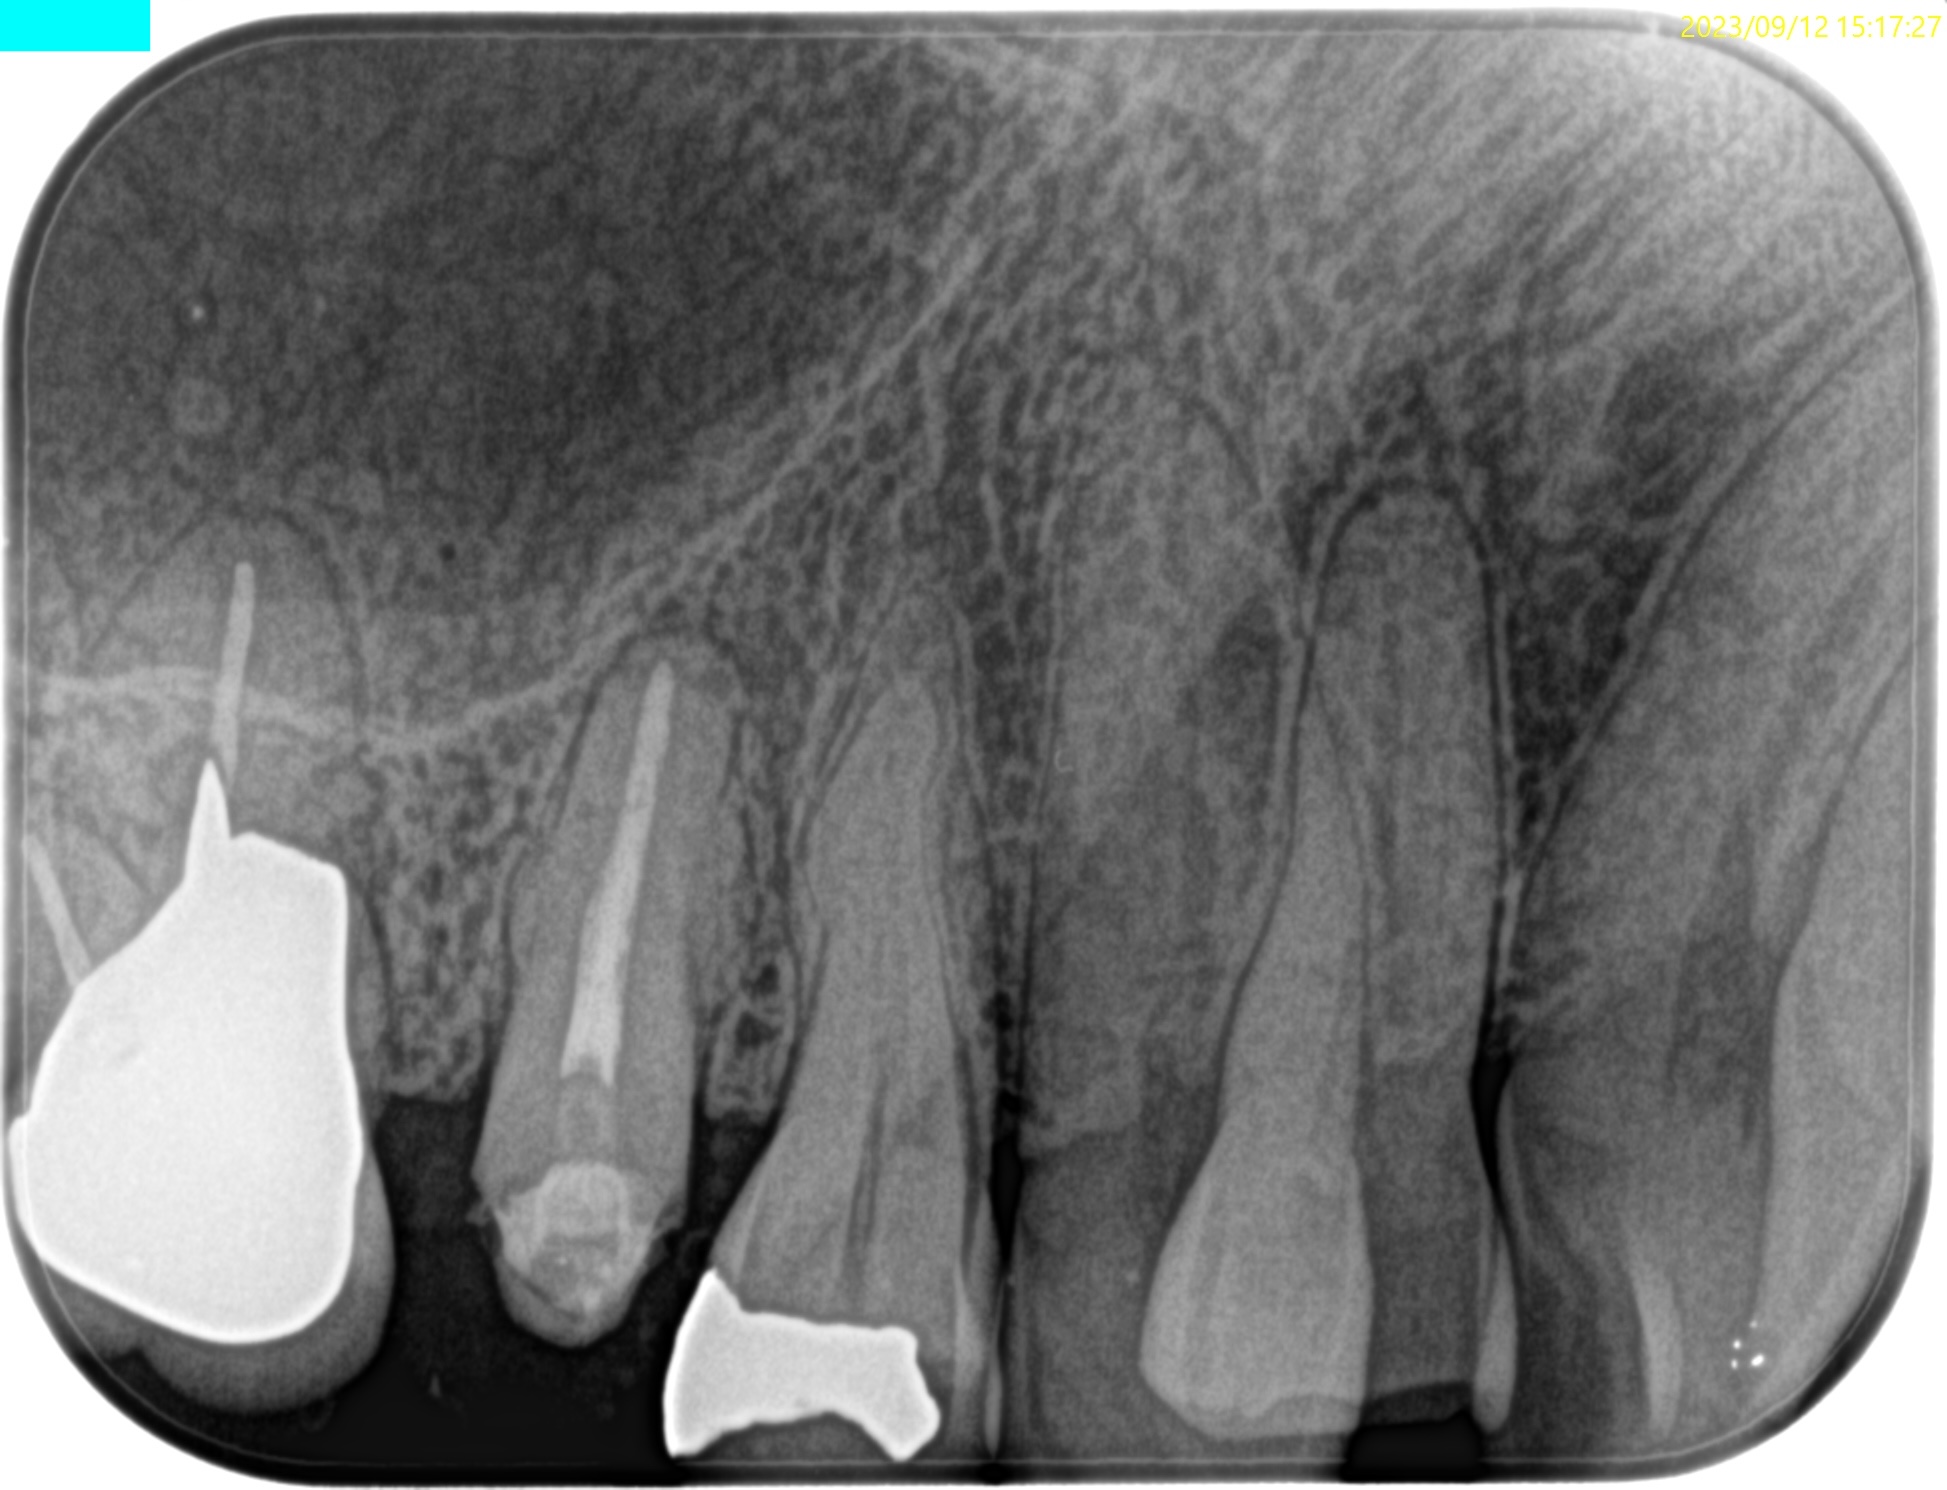

歯内療法学的検査(2023.9.12)

PA(2023.9.12)

CBCT(2023.9.12)

MB

DB

P

Sinus tractがあり、

既根管治療歯であるが、

歯根が折れているような画像所見はない。

こういうものを見るときのポイントは、根管口部だ。

この方は、#19も治療が必要であったが、

根管口部が大きく削られている。こういうことをやると、歯牙が垂直的に破断することが多い。

根管治療がしやすくなるから、という理由で根管口部を多く削ることは許されない

のだが…

歯内療法学的診断(2023.9.12)

Pulp Dx: Previously treated

Periapical Dx: Chronic apical abscess

Recommended Tx: Core build up→Apicoectomy